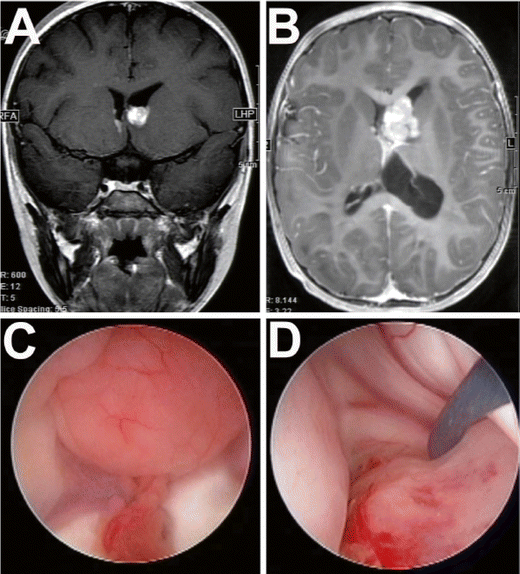

Seven-year-old with tuberous sclerosis and intraventricular tubers and a radiologically growing subependymal giant cell astrocytoma. The coronal (a) and axial post contrast MRI (b) demonstrates the intraventricular lesions. Endoscopic view of the lesions (c) and endoscopic-assisted microsurgical resection of the tumor (d)